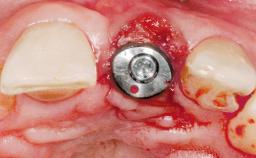

Late Flapless Placement of an Implant in a Maxillary Left Central Incisor Site

A 39-year-old male patient presented with a chief complaint of discomfort and gingival discoloration around his maxillary left central incisor. He was in good general health and was a non-smoker. His past dental history was significant because of the traumatic fracture of tooth 21 in a sporting accident at age 13. Initial dental treatment included endodontic therapy and a full-coverage restoration. The patient became symptomatic 5 years later, when structural failure of the tooth resulted in the dislodgment of the crown. Endodontic retreatment, apical surgery, and post-and-core restoration were performed.

Placement Protocol Early or late implant placement

Bone Volume Deficient horizontally, requiring prior grafting